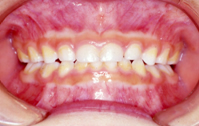

叢生(前歯のデコボコ) 8歳女子

治療前

治療後

①主訴:前歯の不揃いを治したい

②診断名あるいは主な症状:前歯部の叢生(アゴと歯の大きさの不調和)

③年齢:8歳

④治療に用いた主な装置:ライトワイヤー法

⑤抜歯部位:非抜歯

⑥治療期間:約1年半

⑦治療費:検査:38,500円

基本矯正費用:440,000円~

調整料:6,600円 (ひと月に1回)

⑧リスクと副作用:治療開始後数日は噛むときに痛みがあります。

虫歯予防のため適切な歯磨きが必要

装置が破損することがあるため、その時は連絡をすること

後戻り防止のため、保定装置の装着が必要である。

第2期(永久歯列期)での仕上げの治療が必要になる場合もある